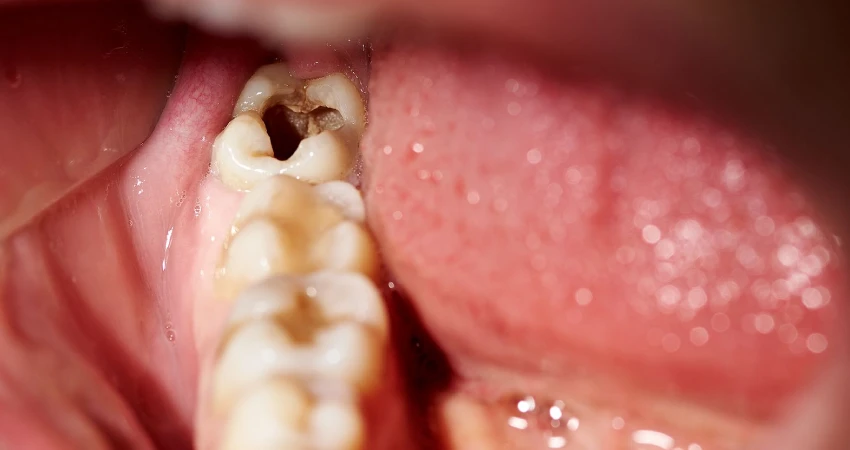

مع تطور تسوس الأسنان العميق تبدأ الأعراض بالظهور بشكل أوضح وتتحول من انزعاج بسيط إلى ألم مستمر ومزعج. من أبرز العلامات الشعور بألم حاد أو نابض في السن خاصة عند تناول الأطعمة أو المشروبات الباردة أو الساخنة أو الحلوة، وقد يستمر الألم حتى بعد انتهاء التحفيز.

كما يلاحظ المريض ازدياد حساسية الأسنان، وظهور ثقوب أو تجاويف واضحة في الضرس أو السن المصاب، مع تغيّر لونه إلى البني أو الأسود أحيانًا. في مراحل أكثر تقدمًا قد يحدث ألم عند الضغط على السن أثناء المضغ، أو انتفاخ واحمرار في اللثة المحيطة به، مع احتمال ظهور رائحة فم كريهة بسبب تكاثر البكتيريا داخل التسوس العميق.